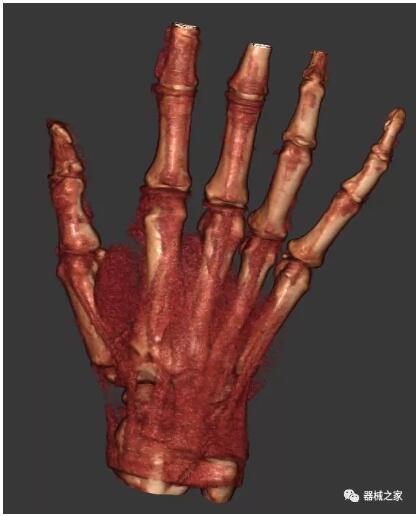

以上介紹的CT均來自國外同一家公司,這些CT均配置了可視化軟件,可以進行切片、3D重建以及大型CT附帶的所有典型的操作功能。

以下是這些“特立獨行”的CT所拍出來的圖像: